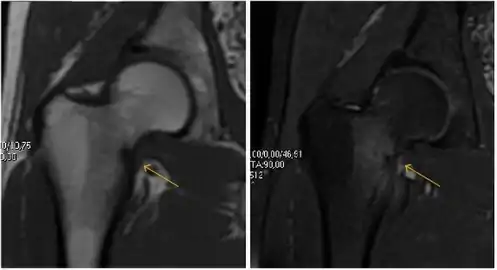

Most of the angles and measurements described in the plain radiograph section can be accurately reproduced on MRI. In addition, the superiority of MRI resolution with intra-articular contrast allows detection of labral and chondral abnormalities that may influence the choice of medical, percutaneous, or surgical management (Figure 9).[1]

Figure 9:

Sagittal T1 weighted image showing anterosuperior labral tear.[1]

Sagittal T1 weighted image showing chondral lesion.[1]

Sagittal CT-arthrography showing posteroinferior chondral injury.[1]

Coronal CT-arthrography (d) showing ligamentum teres tear.[1]

MR arthrography has proven superior in accuracy when compared to native MR imaging. It is considered the best technique to assess the labrum. Knowledge of the normal variable morphology of the labrum helps to differentiate tears from normal variants. A triangular shape is most commonly seen in 66% of asymptomatic volunteers, but round, flattened, and absent labra can also be found in asymptomatic populations. MR arthrography has demonstrated sensitivity over 90% and specificity close to 100% in detecting labral tears. Loose bodies are demonstrated as filling defects surrounded by the hyperintense gadolinium.[1]

Association between labral tears and chondral damage has been demonstrated. This underscores the interaction between cartilage and labrum damage in the progression of osteoarthritis. Chondral damage to the posteroinferior part of the acetabulum as a contrecoup lesion occurs in approximately one-third of pincer cases secondary to persistent abutment on the anterior part of the joint leading to a slight posteroinferior subluxation. This is considered a bad prognosis sign.[1]

MR arthrography can also demonstrate ligamentum teres rupture or capsular laxity, which are debated causes of microinstability of the hip. Elongation of the capsule or injury to the iliofemoral ligament or labrum may be secondary to microtrauma in athletes. MR can demonstrate abnormalities in these cases, such as increased joint volume or a ligamentum teres tear (Figure 9).[1]